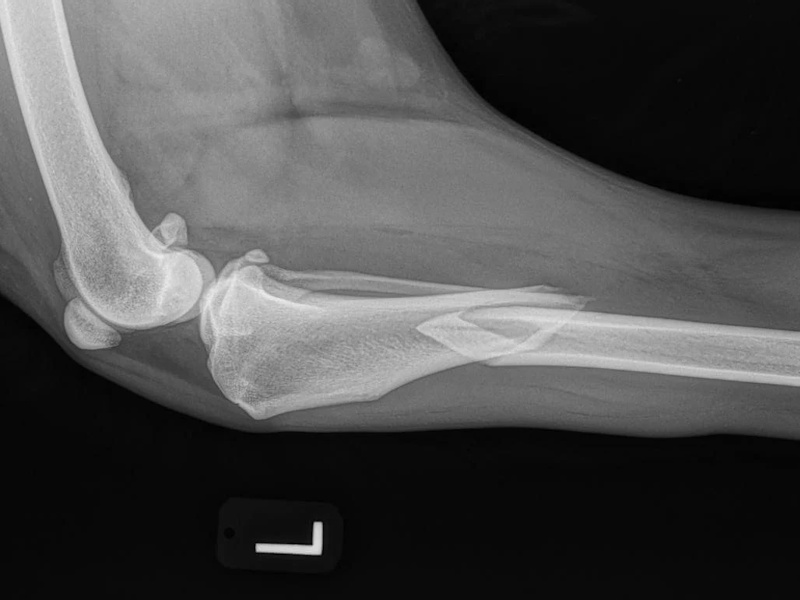

- Ununited Anconeal Process (UAP): Fragment removal $4,500 per elbow